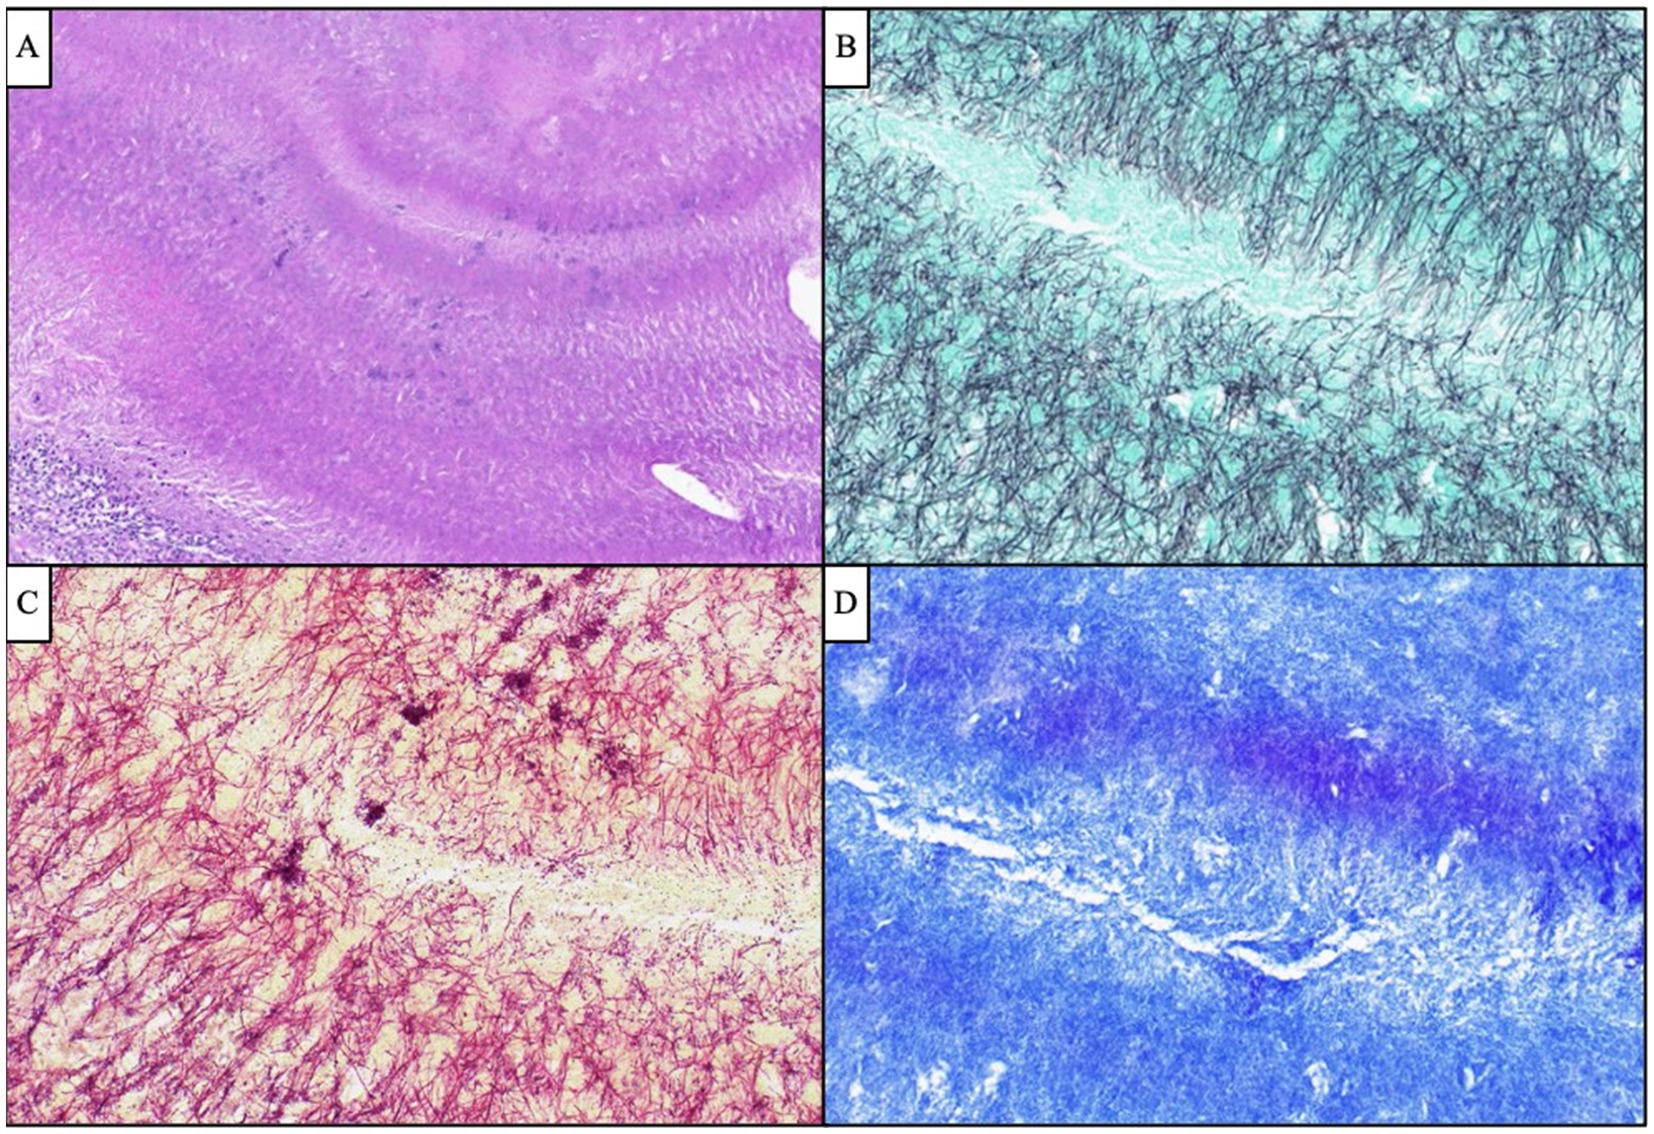

Given the patient’s worsening clinical symptoms and negative microbiologic workup, a serologic NGS test (Karius Test) was performed, which returned positive for Actinomyces israelii at 61 DNA molecules per microliter (MPM) and human herpesvirus 7 (HHV7) at 30 DNA MPM. The pathogenicity of Actinomyces was undetermined, while HHV7 was thought to be incidental. To confirm clinical significance, a transsphenoidal skull base incision and drainage were performed, revealing a necrotic-appearing pituitary gland and readily expressed purulent fluid. Pathological examination showed sulfur granule-like aggregates of branching filamentous bacteria consistent with Actinomyces (Figure 4). Targeted tissue NGS (Broad-Range PCR) also revealed trace Actinomyces israelii, further confirming the diagnosis of CNS actinomycosis. Broad-spectrum antibiotics were narrowed to IV ceftriaxone. Antibiotics were not further narrowed due to the presence of Gram-indeterminate cocci, which were suspected to represent either a secondary bacterial infection or dysmorphic actinomyces. Given the extensive infarcts involving the basal ganglia, thalami, brainstem, and cortices, the family elected to pursue comfort measures. The patient expired shortly after compassionate extubation, approximately 9 days after the suspected diagnosis of CNS actinomycosis. The autopsy revealed diffuse edema and purulence at the skull base, with areas of necrosis and inflammation extending to the walls of the large-caliber vessels. There were regions showing signs of subacute infarcts and meningitis as well. The cause of death was determined to be brain abscess formation with subsequent acute and chronic meningitis (Figure 5). A timeline of the patient’s disease course is provided in Figure 6.

Figure 4. Antemortem lateral skull base endonasal biopsy demonstrated “sulfur granule”-like aggregates of branching filamentous bacteria (A, H&E, 100x), which were GMS-positive (B, 400x) Gram-indeterminate (C, 400x), and FITE-negative (D, 400x), compatible with Actinomyces species. Scattered and clustered cocci were also visualized by Gram stain (C, 400x).